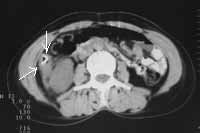

В 10-ти случаях выявлены признаки характерные для рака ободочной кишки: неравномерное утолщение стенок ободочной кишки от 1,0 до 2,6см, нечеткость контуров, повышение плотности окружающей клетчатки, уплотнение переднего листка околопочечной фасции (в случаях рака восходящей и нисходящей кишок) (Рис. 1- 4). В 2-х случаях рак ободочной кишки сопровождался  признаками кишечной непроходимости (Рис. 5). В одном случае массивная опухоль исходила из правой почки и вовлекала восходящую кишку. В другом — выявлена опухоль имеющая неоднородную мягкотканную плотность, относительно четкие контуры расположенная, премущественно экстраорганно по отношению к нисходящей кишке (Рис. 6). В одном случае при пероральном контрастировании ободочной кишки создалось впечатление ракового поражения селезеночного угла толстой кишки, для уточнения исследование повторили после очистительной клизмы и раздувания — в результате выявлен полип на ножке (Рис. 7). При обследовании постоперационных больных — в 1-м случае выявлен околоободочный абсцесс, в другом — явления анастомозита после левосторонней гемиколонэктомии, проявляющегося утолщением стенок кишки в зоне анастомоза до 6мм с выраженным расширением проксимальной части кишки. В двух случаях при КТ исследовании не получено убедительных данных за опухолевое поражение ободочной кишки хотя данные колоноскопии указывали на раковое заболевание или малигнизированный полип.

Рис. 4. Рак восходящей кишки: неравномерное утолщение стенок (стрелки) с инфильтрацией переднего листка околопочечной фасции и околопочечной клетчатки.